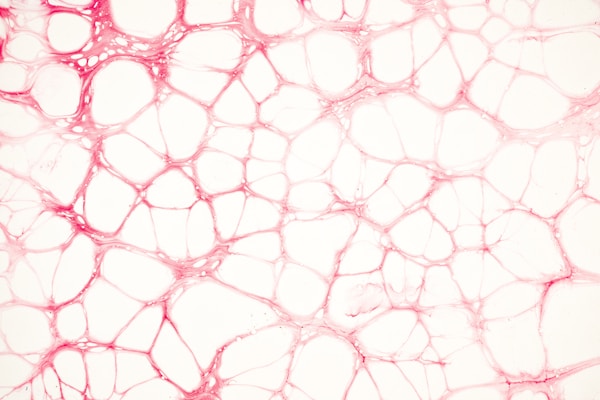

Nicotinamide adenine dinucleotide is an essential coenzyme found in all living cells. It is required for a multitude of essential metabolic reactions, including the conversion of nutrients into energy, which is required for daily physiological functions.

NAD is a vital part of the cellular energy production process, which provides our cells with the energy needed to sustain life. Cellular energy is derived from the food we eat, and through a series of complex chemical reactions, our body produces a molecule called ATP (adenosine triphosphate). NAD plays a crucial role in this process by transferring electrons between different molecules, thereby generating energy.

By ensuring our body has a sufficient supply of NAD, we can support our cells’ continuous energy production, thereby promoting optimal health and protecting against certain conditions like metabolic and chronic exhaustion.